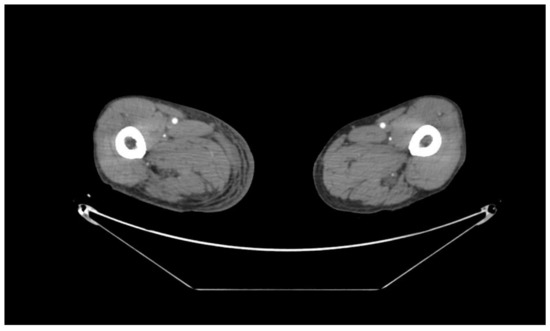

3.1. Case Report